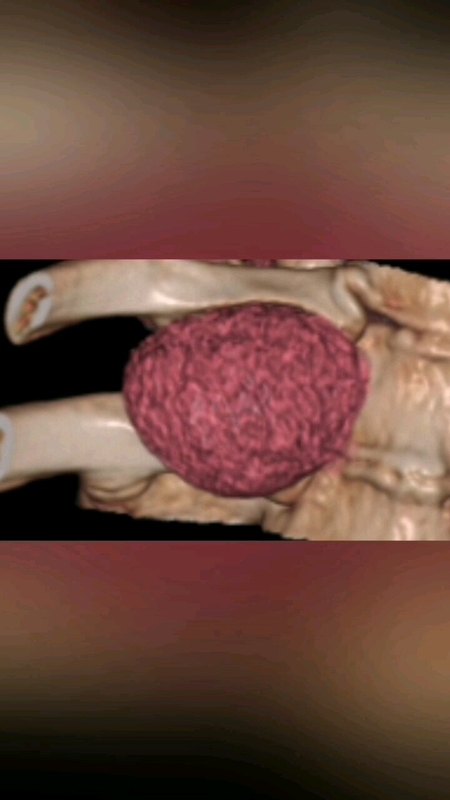

脊柱也長腫瘤嗎?